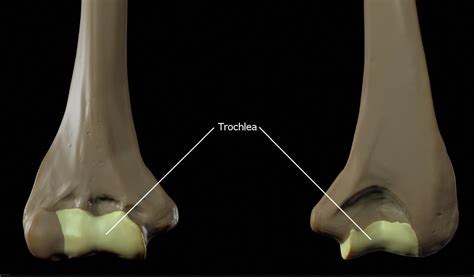

The trochlea of humerus is a prominent feature of the distal humerus, the bone that forms the upper arm. It is a smooth, concave groove that runs from the medial to the lateral side of the humerus. This groove articulates with the trochlear notch of the ulna, forming the humeroulnar joint. The trochlea is bordered by the medial and lateral epicondyles, which provide attachment points for various muscles and ligaments.